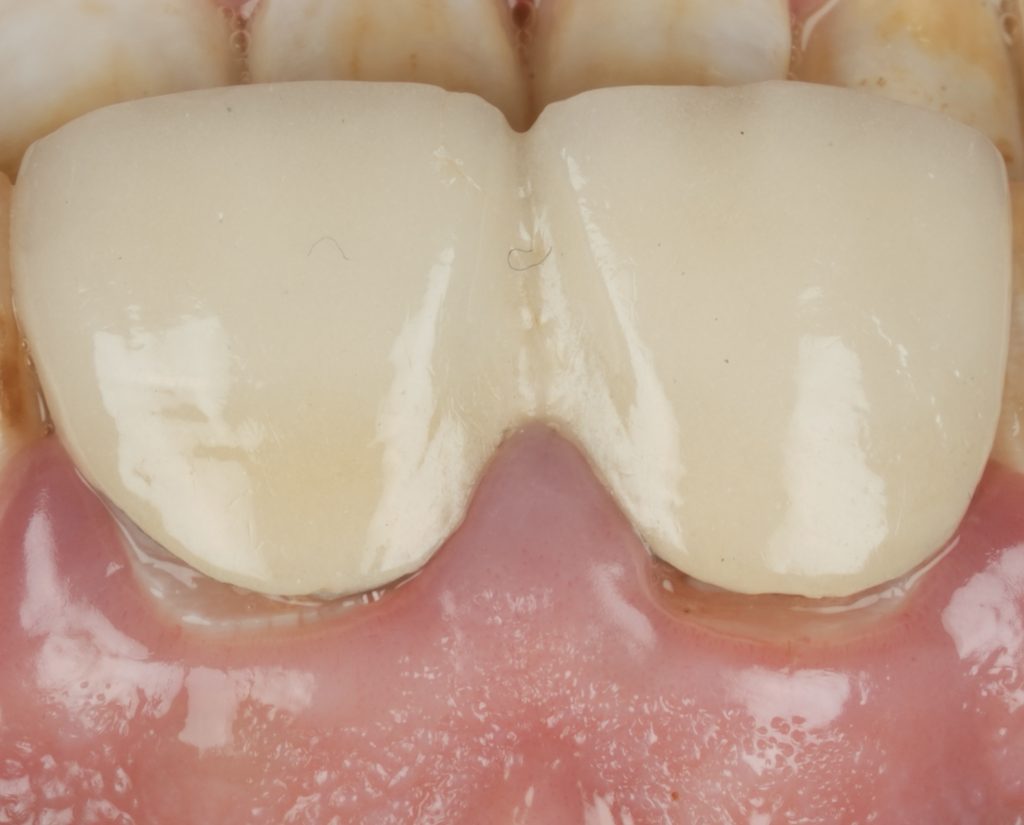

6️⃣ Finishing, Texture & Integration

Margins were refined using fine diamond strips, and surface gloss was enhanced with a multi-step polishing system (Shofu OneGloss + OptraPol Next Gen). Post-operative evaluation showed ideal incisal translucency, line-angle symmetry, and gingival health (Fig 5 & 6).